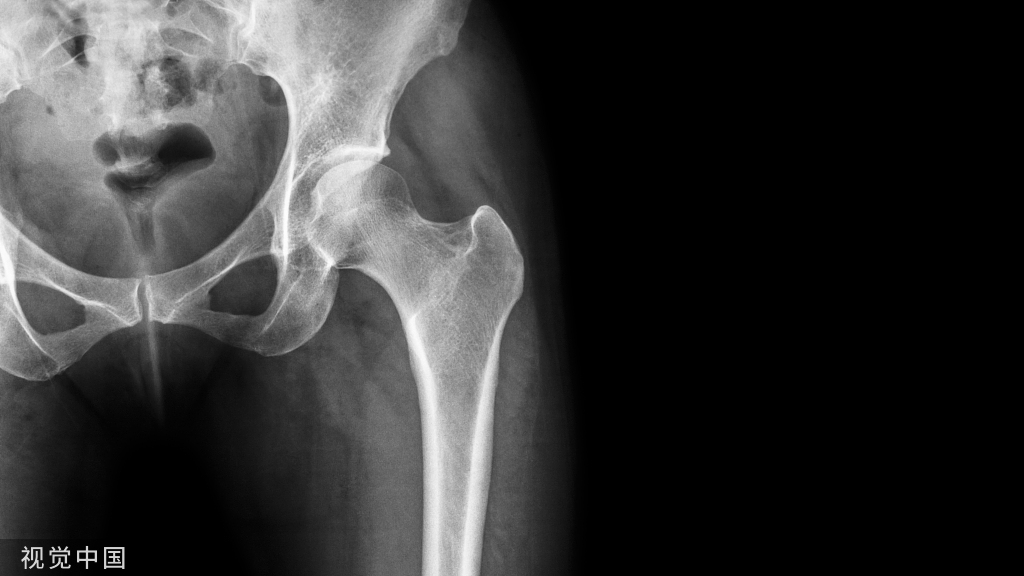

13肿瘤

• 肩关节肿瘤发病率,仅次于膝关节

• 良性骨肿瘤除非压迫皮肤或神经或恶变,都无明显疼痛

• 恶性骨肿瘤 原发、继发

原发性恶性骨肿瘤1.大多单发2.局部疼痛严重,初为间歇性,以后为持续性,非甾药不能缓解3.局部表浅静脉或毛细血管网可扩张,皮温升高,压痛明显,甚至可摸到震颤或听到杂音。4.多见于骨软骨瘤、骨肉瘤、骨巨细胞瘤

• X线:可以提示肿瘤的良恶性,甚至作出较明确的诊断

• CT、MRI:可清晰提示肿瘤范围,血运丰富与否,与邻近组织、器官的关系,有助于手术治疗

• 确诊依据:病理组织学检查